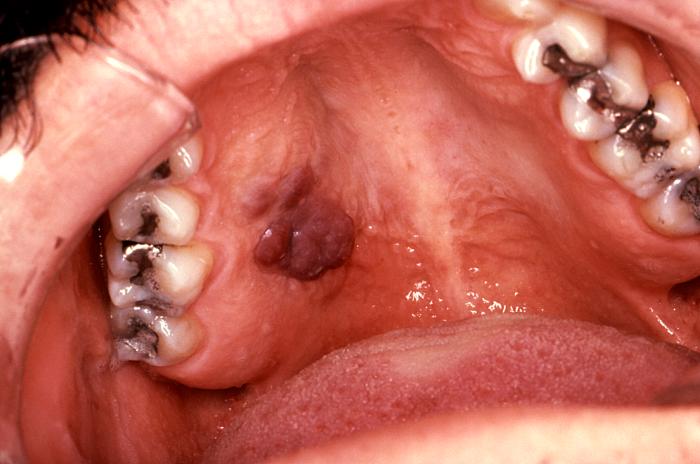

Sarcoma de Kaposi |

El sarcoma Kaposi es la neoplasia intraoral más común que se observa en el SIDA y generalmente se presenta en el paladar duro, encías y zona del trígono retromolar, como una mancha violácea o rojiza, de límite difuso, indolora, que en el 20% de los casos puede ser la primera manifestación. Esta neoplasia a veces presenta un aspecto tumoral, pero muchas veces se observa como una mácula rojiza, en el primer caso tiene un peor pronóstico. Este tumor es multifocal y en la boca puede observarse varias lesiones en paladar y/o encía, aunque lo más frecuente es que el paciente tenga otras lesiones en piel de extremidades superiores, torax y cara. Histológicamente este tumor presenta una proliferación de células fusadas, más o menos arremolinadas, con formaciones de múltiples espacios vasculares, con células endoteliales atípicas, y abundante hemorragia. Esta lesión está asociada a VIH en la mayoría de los pacientes, y era tratada en un principio con inyecciones intralesionales de citostático, esta práctica ya no se realiza debido a que la terapia antiretrovial produce su involución hasta que desaparece de la mucosa bucal. En otras ubicaciones, como en la mucosa esofágica es necesario realizar quimioterapia sistémica, para su tratamiento.